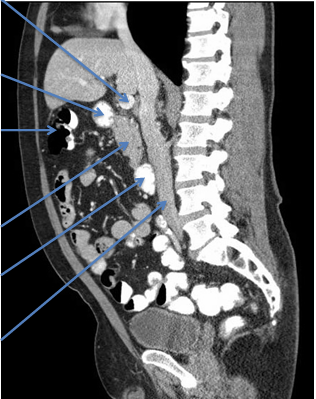

General info on pancreas:

-posterior to stomach

-neck of pancreas is ANTERIOR to superior mesenteric artery/vein

-tail = peritoneal

-everything else = retroperitoneal

-linguila (uncinate process) = posterior to superior mesenteric artery